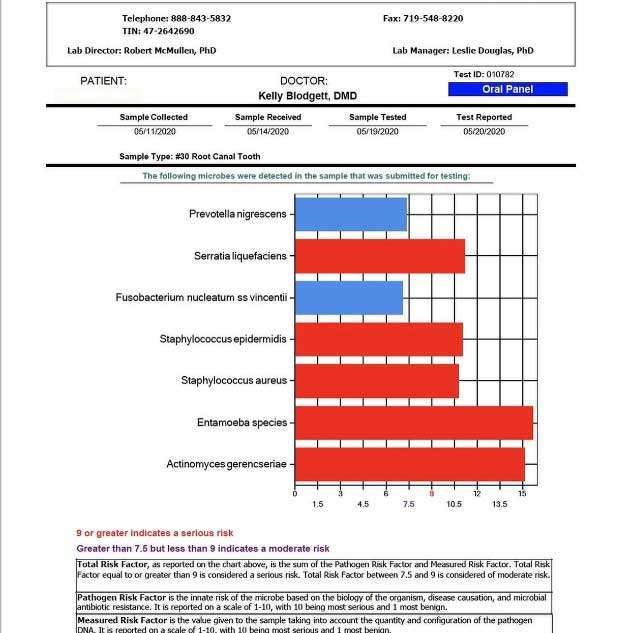

Silent inflammation due to root canal therapy, cavitation (avascular osteonecrosis) and titanium implants leads to immune system activation. The intraoral interference fields created by metals, NICOs, bacteria in root canal treated teeth produce highly toxic hydrogen sulfides (Thioether/Mercaptan), metals show cytotoxic, immunological and carcinogenic effects and NICOs (Neuralgia inducing osteonecrosis) consist of increased inflammatory mediators like RANTES, FGF-2 and IL-1ra.